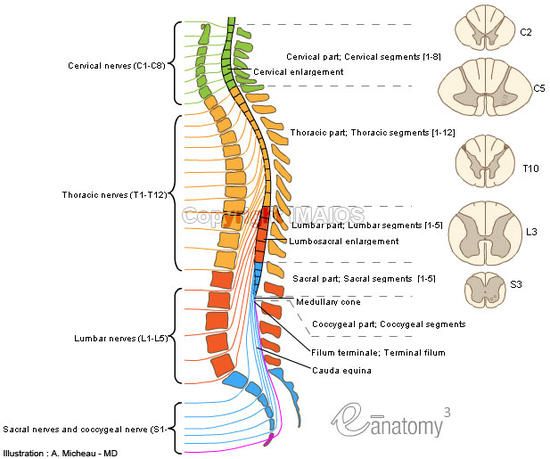

2. Conus Medullaris - tapered end at L1, L2 level – lumbar enlargement, length of cord is determined by age 4, it does not continue to grow

3. Cauda equina - fibrous strands extending from conus medullaris to coccyx ("horses tail”)--long ventral and dorsal roots.